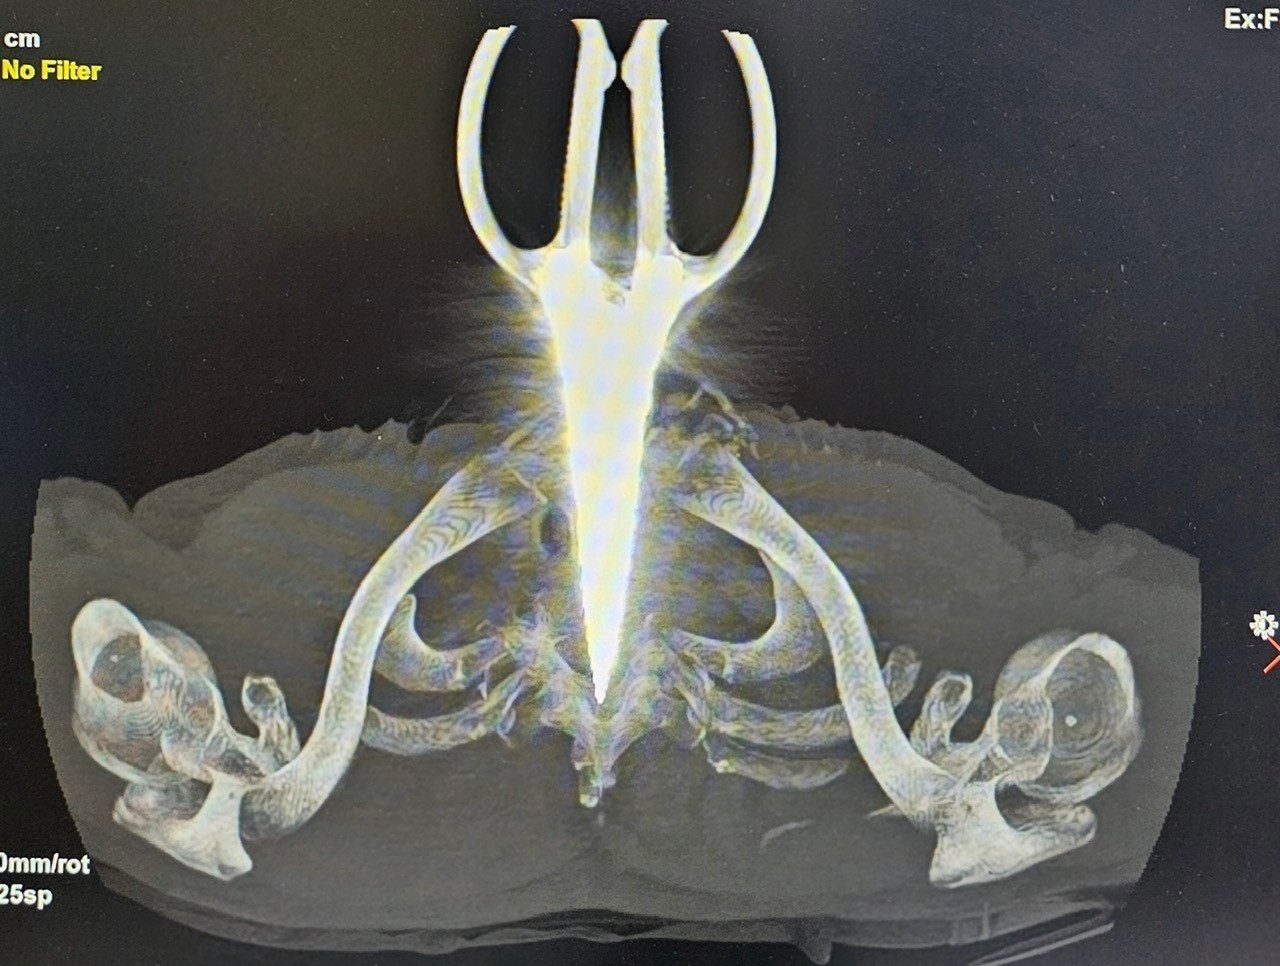

| Ảnh phim X-Quang cây kéo dài 24cm đâm cổ bệnh nhân. |

Kết quả X-Quang và chụp cắt lớp vi tính ghi nhận, dị vật kim loại xuyên giữa cột sống ngực D1 của anh H. Sau hơn 2 giờ phẫu thuật, chiếc kéo đã được lấy thành công khỏi người anh H., cùng với việc xử lý các tổn thương khác của bệnh nhân.